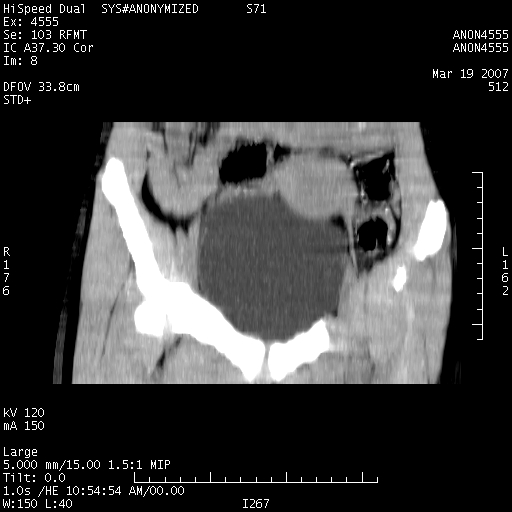

女,14岁,腹痛腹胀月余,患者发育正常,无月经史,检查发现下腹部肿块。患者碘过敏试验阳性。

子宫处见大的软组织肿块,考虑患者女性、14岁无月经,怀疑子宫发育异常

处女膜闭锁,阴道积血。

从矢状位上可见阴道部位明显增粗,内容密度较低,结合患者年龄和临床表现,首先考虑为先天性处女膜闭锁。

处女膜闭锁,阴道、子宫积血。

结合病史考虑处女膜闭锁致阴道、子宫积血。

处女膜闭锁致阴道、子宫积血。

考虑为先天性处女膜闭锁所致的阴道及子宫积血